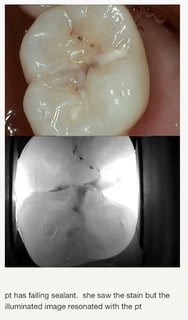

Ces photographies ont été prises avec l’utilisation de la technologie Lum G2. Elles permettent de démontrer son pouvoir dans le diagnostique des caries, des fractures et des fêlures.

Lum Decay Under Sealant - Clinique dentaire Morin-Houle in Hull